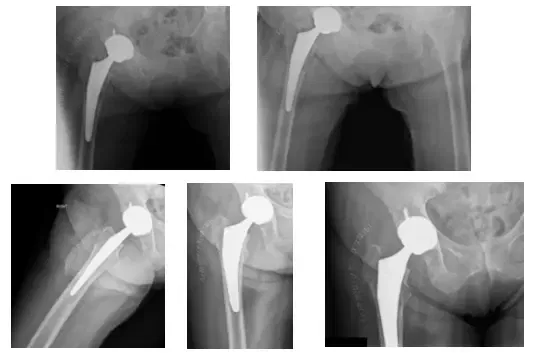

Se aconsejó que se retiraran los herrajes y se sometiera al paciente a una artroplastia total de cadera derecha (ATC).

Antes de la intervención, se aconsejó a la paciente que se sometiera a un aspirado de la cadera derecha para descartar una infección. Los resultados de la aspiración fueron negativos para la infección y la paciente decidió seguir adelante con el procedimiento.

Las radiografías postoperatorias muestran una THA derecha

El paciente había seguido el postoperatorio con un dolor mínimo. El paciente presentaba una buena amplitud de movimiento y soportaba peso según lo toleraba. El paciente ha evolucionado bien posteriormente.